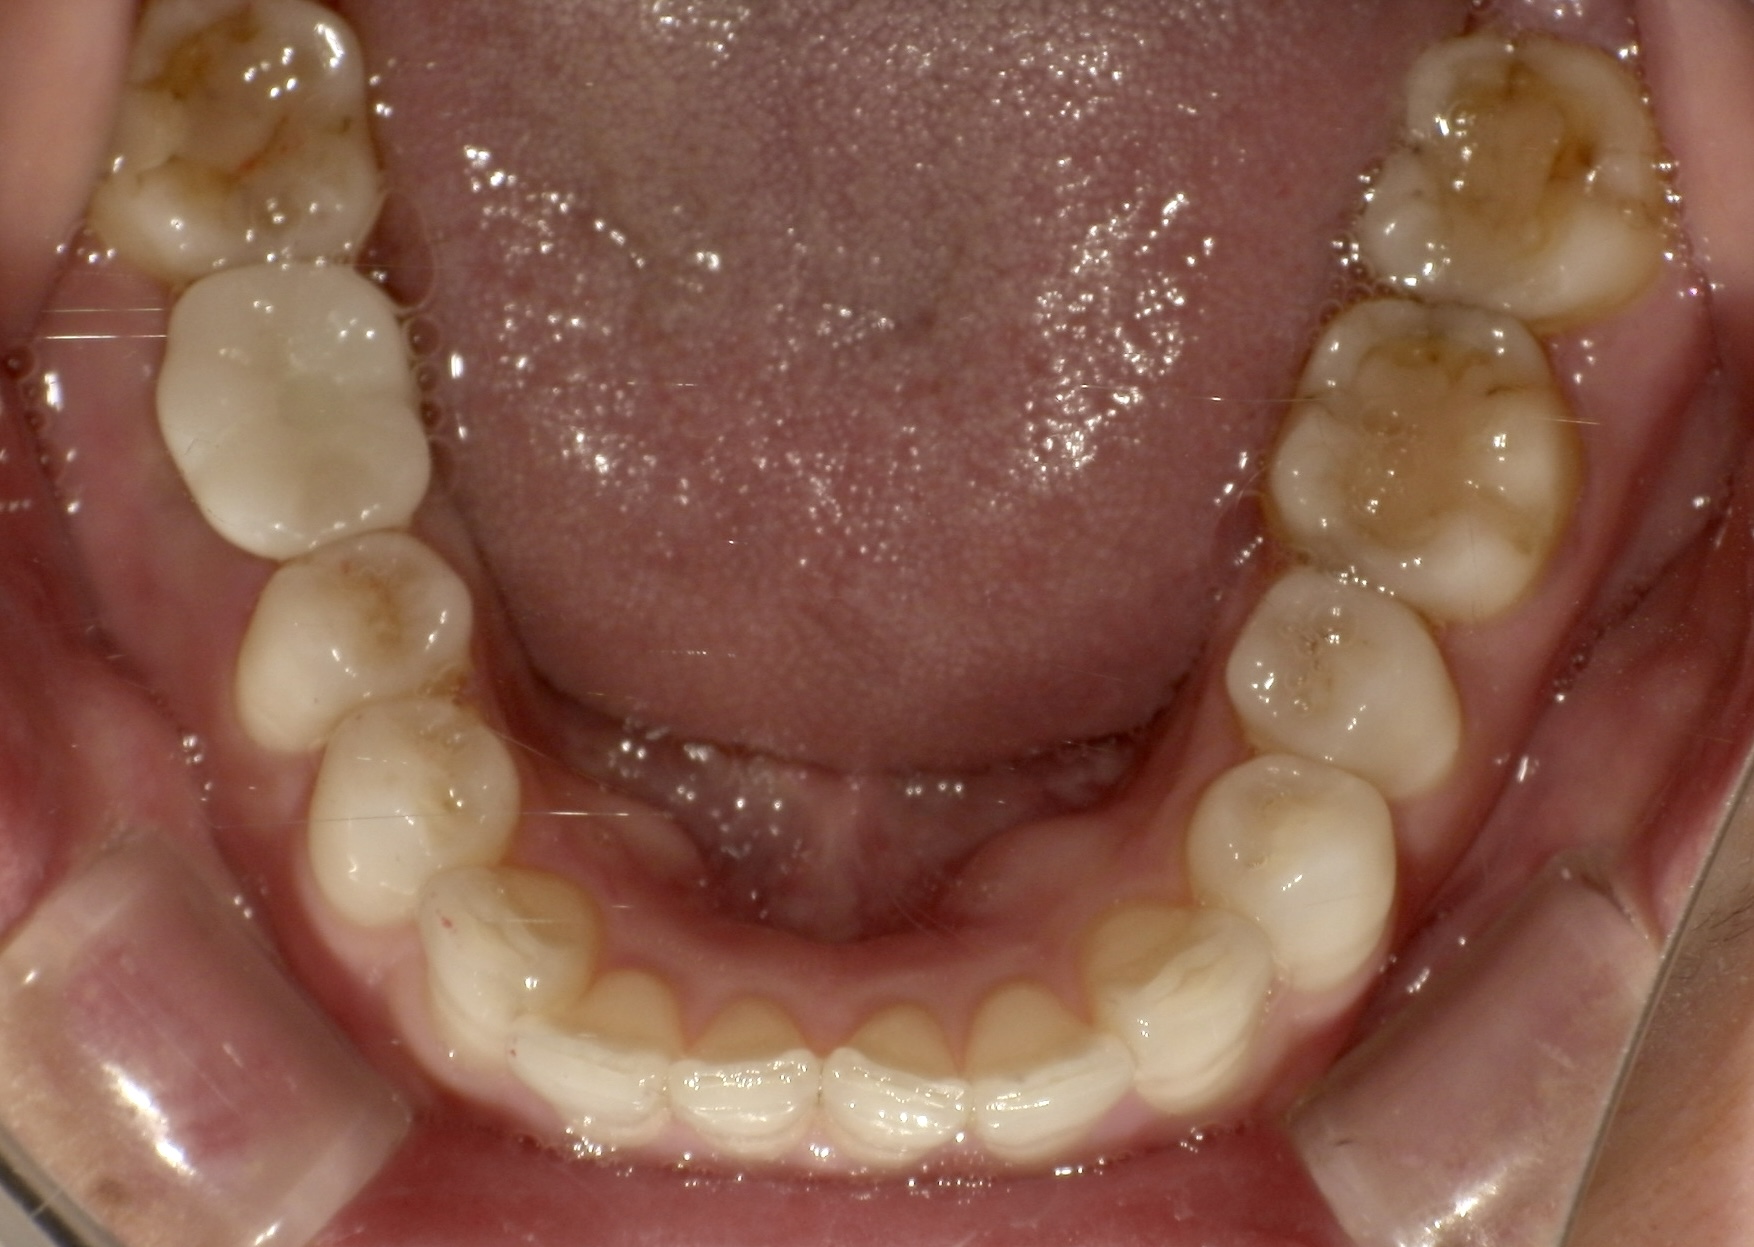

症状 『銀歯が痛くて噛めないので治して欲しい』との訴えで初めて来院 年齢・性別 40代女性 治療期間 約8ヶ月(抜歯する前〜インプラント治療完了まで) 治療方法 一度保存を試みたものの状態が悪く抜歯 その後インプラント治療を希望 費用 インプラント治療代 400,000円+税(手術、薬、被せ物などの費用全て含む) デメリット・注意点 歯が完全に割れていたこともあり骨の状態が非常に悪く、インプラント治療開始までに時間を要した 備考 銀歯が痛くて治して欲しいとのことで来院されました。 レントゲンの様子を見ても歯が割れている可能性は高かったですが、保存できる可能性もあるため一度銀のかぶせものを外して歯の状態を確認しました。 実際、根の状態を見てみるとかなり大きく穴があいていて保存は難しく抜歯することになりました。(下に写真あり) 抜歯後はインプラント治療をご希望されたため、骨を回復させたのちに治療を行いました。 歯の色は患者様のご希望で比較的白い歯の色を選択されました。 食事中も自分の歯のように噛めるとお喜びいただき、現在はメインテナンスに通っていただいており順調です。 -